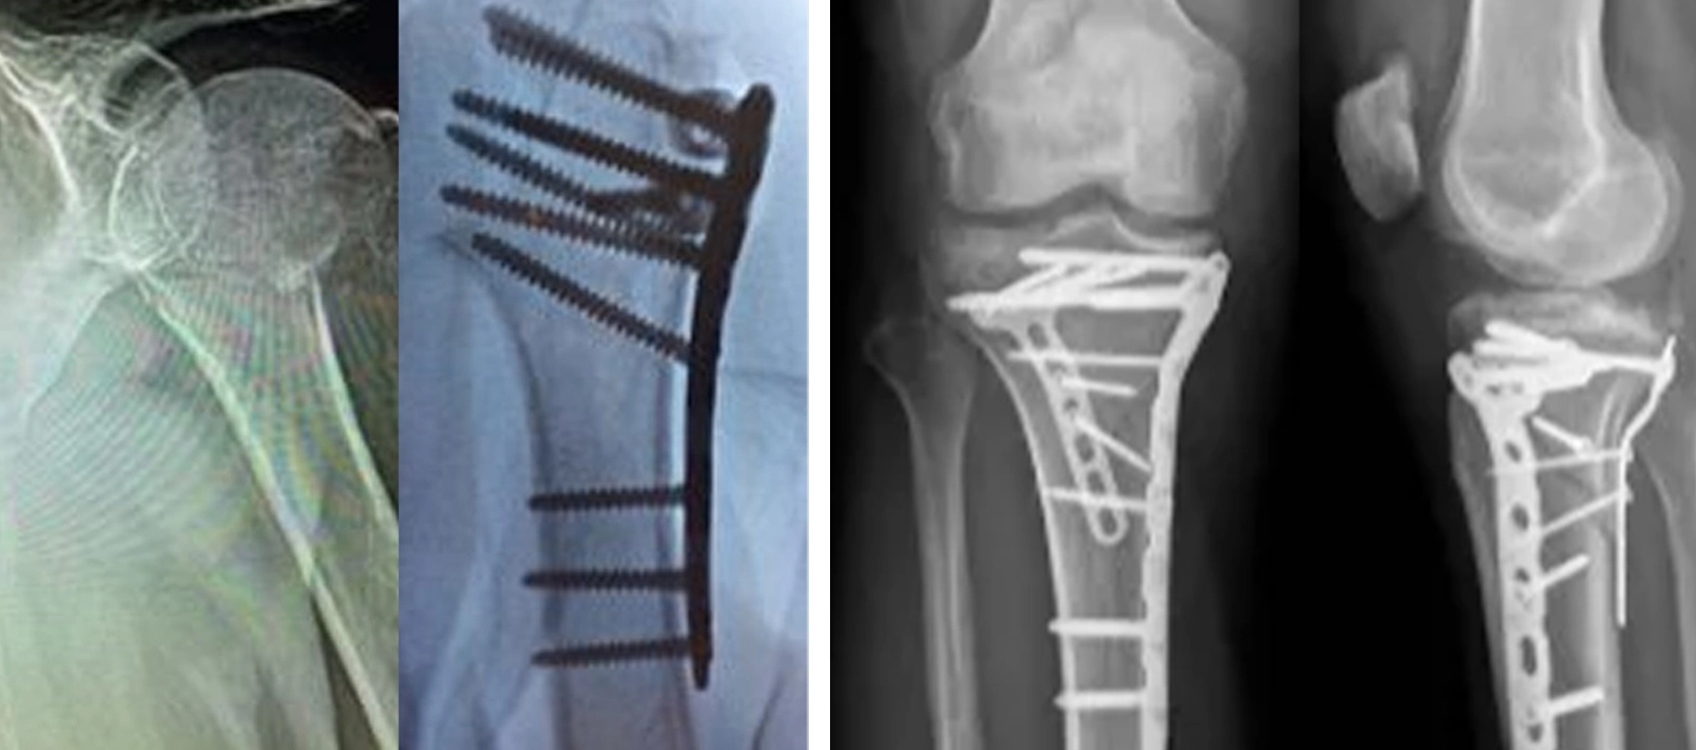

Fijación con placa de bloqueo (ORIF)

La fijación con placa de bloqueo se utiliza ampliamente en las fracturas del húmero proximal, especialmente en el hueso osteoporótico. Proporciona estabilidad angular y permite una movilización temprana.

Cirugía ortopédica de fijación con placa de bloqueo del húmero proximal

Aplicación quirúrgica de fijación con placa de bloqueo del húmero proximal.jpg

Ventajas de los sistemas de placas de bloqueo

• Fijación de alta estabilidad

• Adecuado para hueso osteoporótico

• Diseño de tornillo multiángulo

• Apoya la rehabilitación temprana